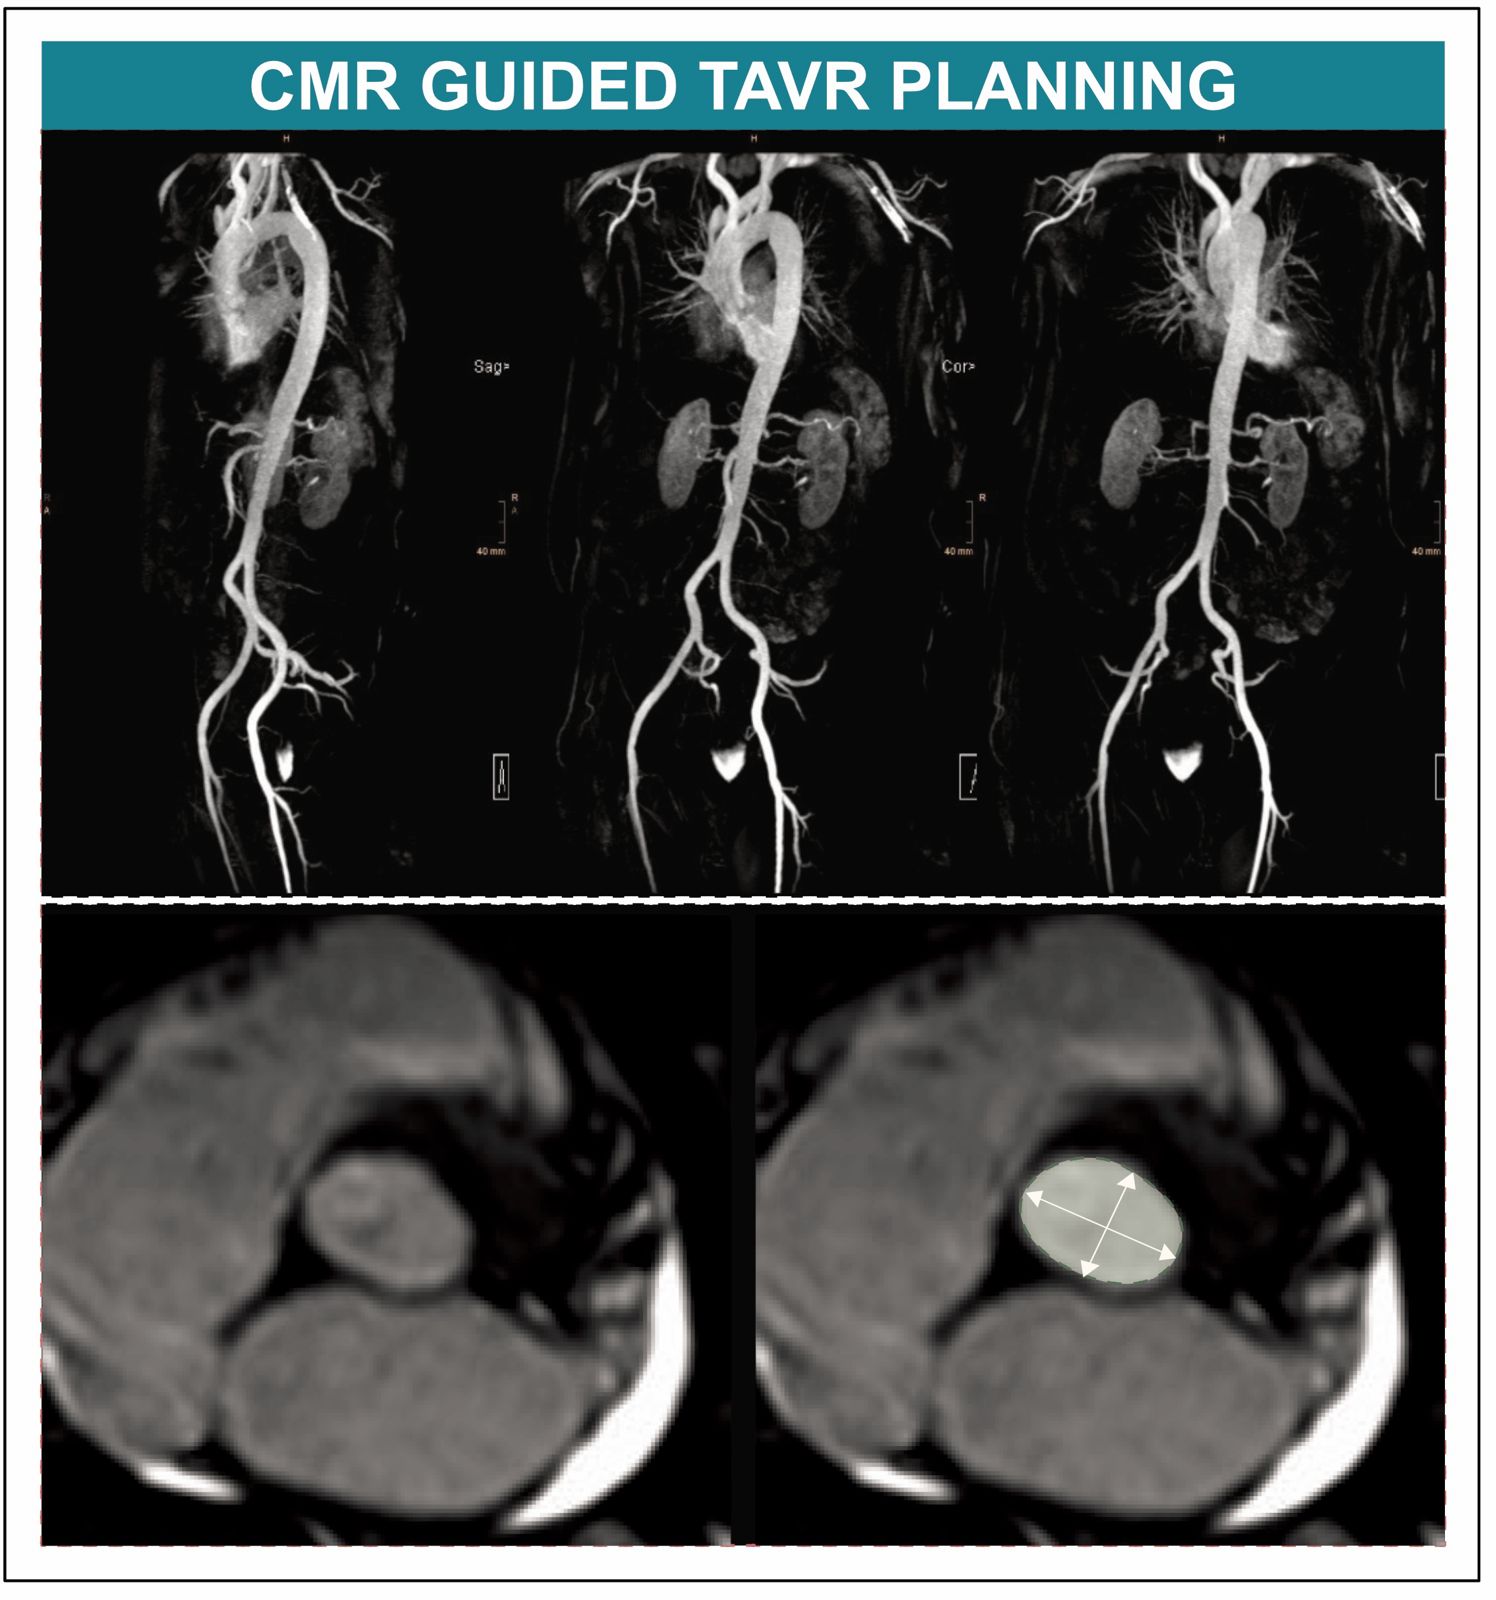

Die Computertomografie (CT) hat sich bei der Vorbereitung von Eingriffen wie dem Transkatheter-Aortenklappenersatz (TAVI) bewährt. Nahezu die Hälfte der Patient:innen mit erworbener Verengung der Herzklappen leidet jedoch an einer chronischen Nierenerkrankung, was gegen den Einsatz von CT-Kontrastmitteln spricht. Eine randomisierte Studie belegt nun erstmals, dass die Kardiale Magnetresonanztomografie für die TAVI-Planung ebenso geeignet ist – ein Lichtblick für eine schonendere TAVI-Abklärung.

Die prä-interventionelle Planung des Eingriffes erfolgt üblicherweise mittels Computertomografie (CT), was für Patient:innen mit Niereninsuffizienz aufgrund des erforderlichen Einsatzes von iodhaltigem Kontrastmittel allerdings eine wesentliche Einschränkung darstellt. „Rund die Hälfte aller TAVI-Kandidatinnen und -Kandidaten leidet an einer Niereninsuffizienz und ist durch den Einsatz jodhaltiger Kontrastmittel im Rahmen einer CT einem erhöhten Risiko für eine Nierenschädigung ausgesetzt. Die Strahlenbelastung im Rahmen des CTs ist ein weiterer Nachteil, vor allem im Lichte der immer jünger werdenden TAVI-Population“, weiß Sebastian Reinstadler von der Innsbrucker Univ.-Klinik für Innere Medizin III (Kardiologie und Angiologie). Agnes Mayr von der Innsbrucker Univ.-Klinik für Radiologie ergänzt: „Die kardiale Magnetresonanztomographie (CMR) bietet sich als vielversprechende strahlenfreie Alternative an, bislang fehlten jedoch randomisierte Daten zum Vergleich der Tauglichkeit von CMR- und CT-gesteuerter TAVI“.

BU: Neue Daten belegen, dass die Kardioale Magnetresonanztomografie bei der Planung einer TAVI keine Nachteile hat. (c)Kardiologie Innsbruck

In einer neuen, kürzlich im anerkannten Fachjournal Circulation veröffentlichen Studie konnte nun erstmals die CMR als gute und klinisch geeignete Alternative für die TAVI-Planung nachgewiesen werden. Für das Kooperationsprojekt zwischen der Univ.-Klinik für Kardiologie und Angiologie und der Univ.-Klinik für Radiologie wurden TAVI-Kandidat:innen an den Herzzentren in Innsbruck und Wels randomisiert und einer CMR-gesteuerten oder einer CT-gesteuerten TAVI-Planung zugeführt. „In der Kohorte mit jenen Patient:innen, die sich einer TAVI unterzogen hatten, konnten wir feststellen, dass die CMR-gesteuerte TAVI der CT-gesteuerten TAVI im Hinblick auf den Implantationserfolg nicht unterlegen war und daher als Alternative zur TAVI-Planung in Betracht gezogen werden kann“ bestätigt Erstautor Martin Reindl, der diese positiven Erkenntnisse gemeinsam mit der von Bernhard Metzler geleiteten Arbeitsgruppe Kardio-MRT am diesjährigen ESC Kongress, dem weltweit führender Kongress im Bereich Kardiologie, in der prominenten „Late Breaking Science“ Session vorstellen konnte.